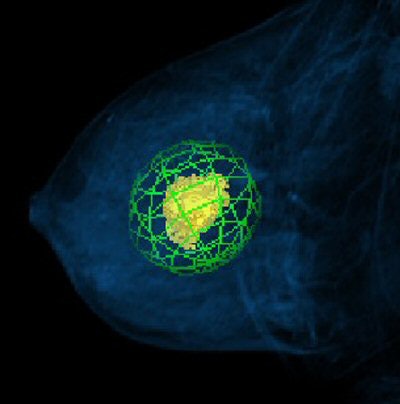

![]() |

| CAD volume summary of a breast MR image. Image courtesy of Seattle Cancer Care Alliance and Confirma. |